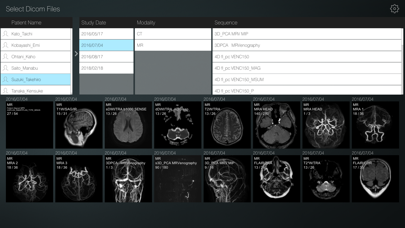

【画像選択モード】

- 医用画像を高速に読み込み、複数の医用画像をすばやく同時に確認することができます。

- 患者名、撮影日、モダリティ、シーケンスごとに表示画像を切り替えることができます。

- 画像を上下にスライドすることでスライスの確認が出来ます。

- 閲覧したい医用画像をタップすると閲覧モードに移行します。

【画像選択モード】

- 医用画像を高速に読み込み、複数の医用画像をすばやく同時に確認することができます。

- 患者名、撮影日、モダリティ、シーケンスごとに表示画像を切り替えることができます。

- 画像を上下にスライドすることでスライスの確認が出来ます。

- 閲覧したい医用画像をタップすると閲覧モードに移行します。